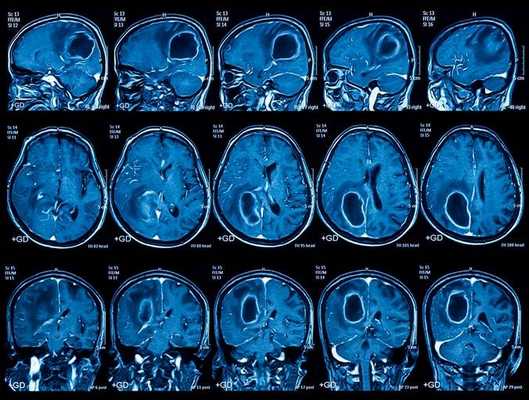

Опухоль на томограмме головного мозга